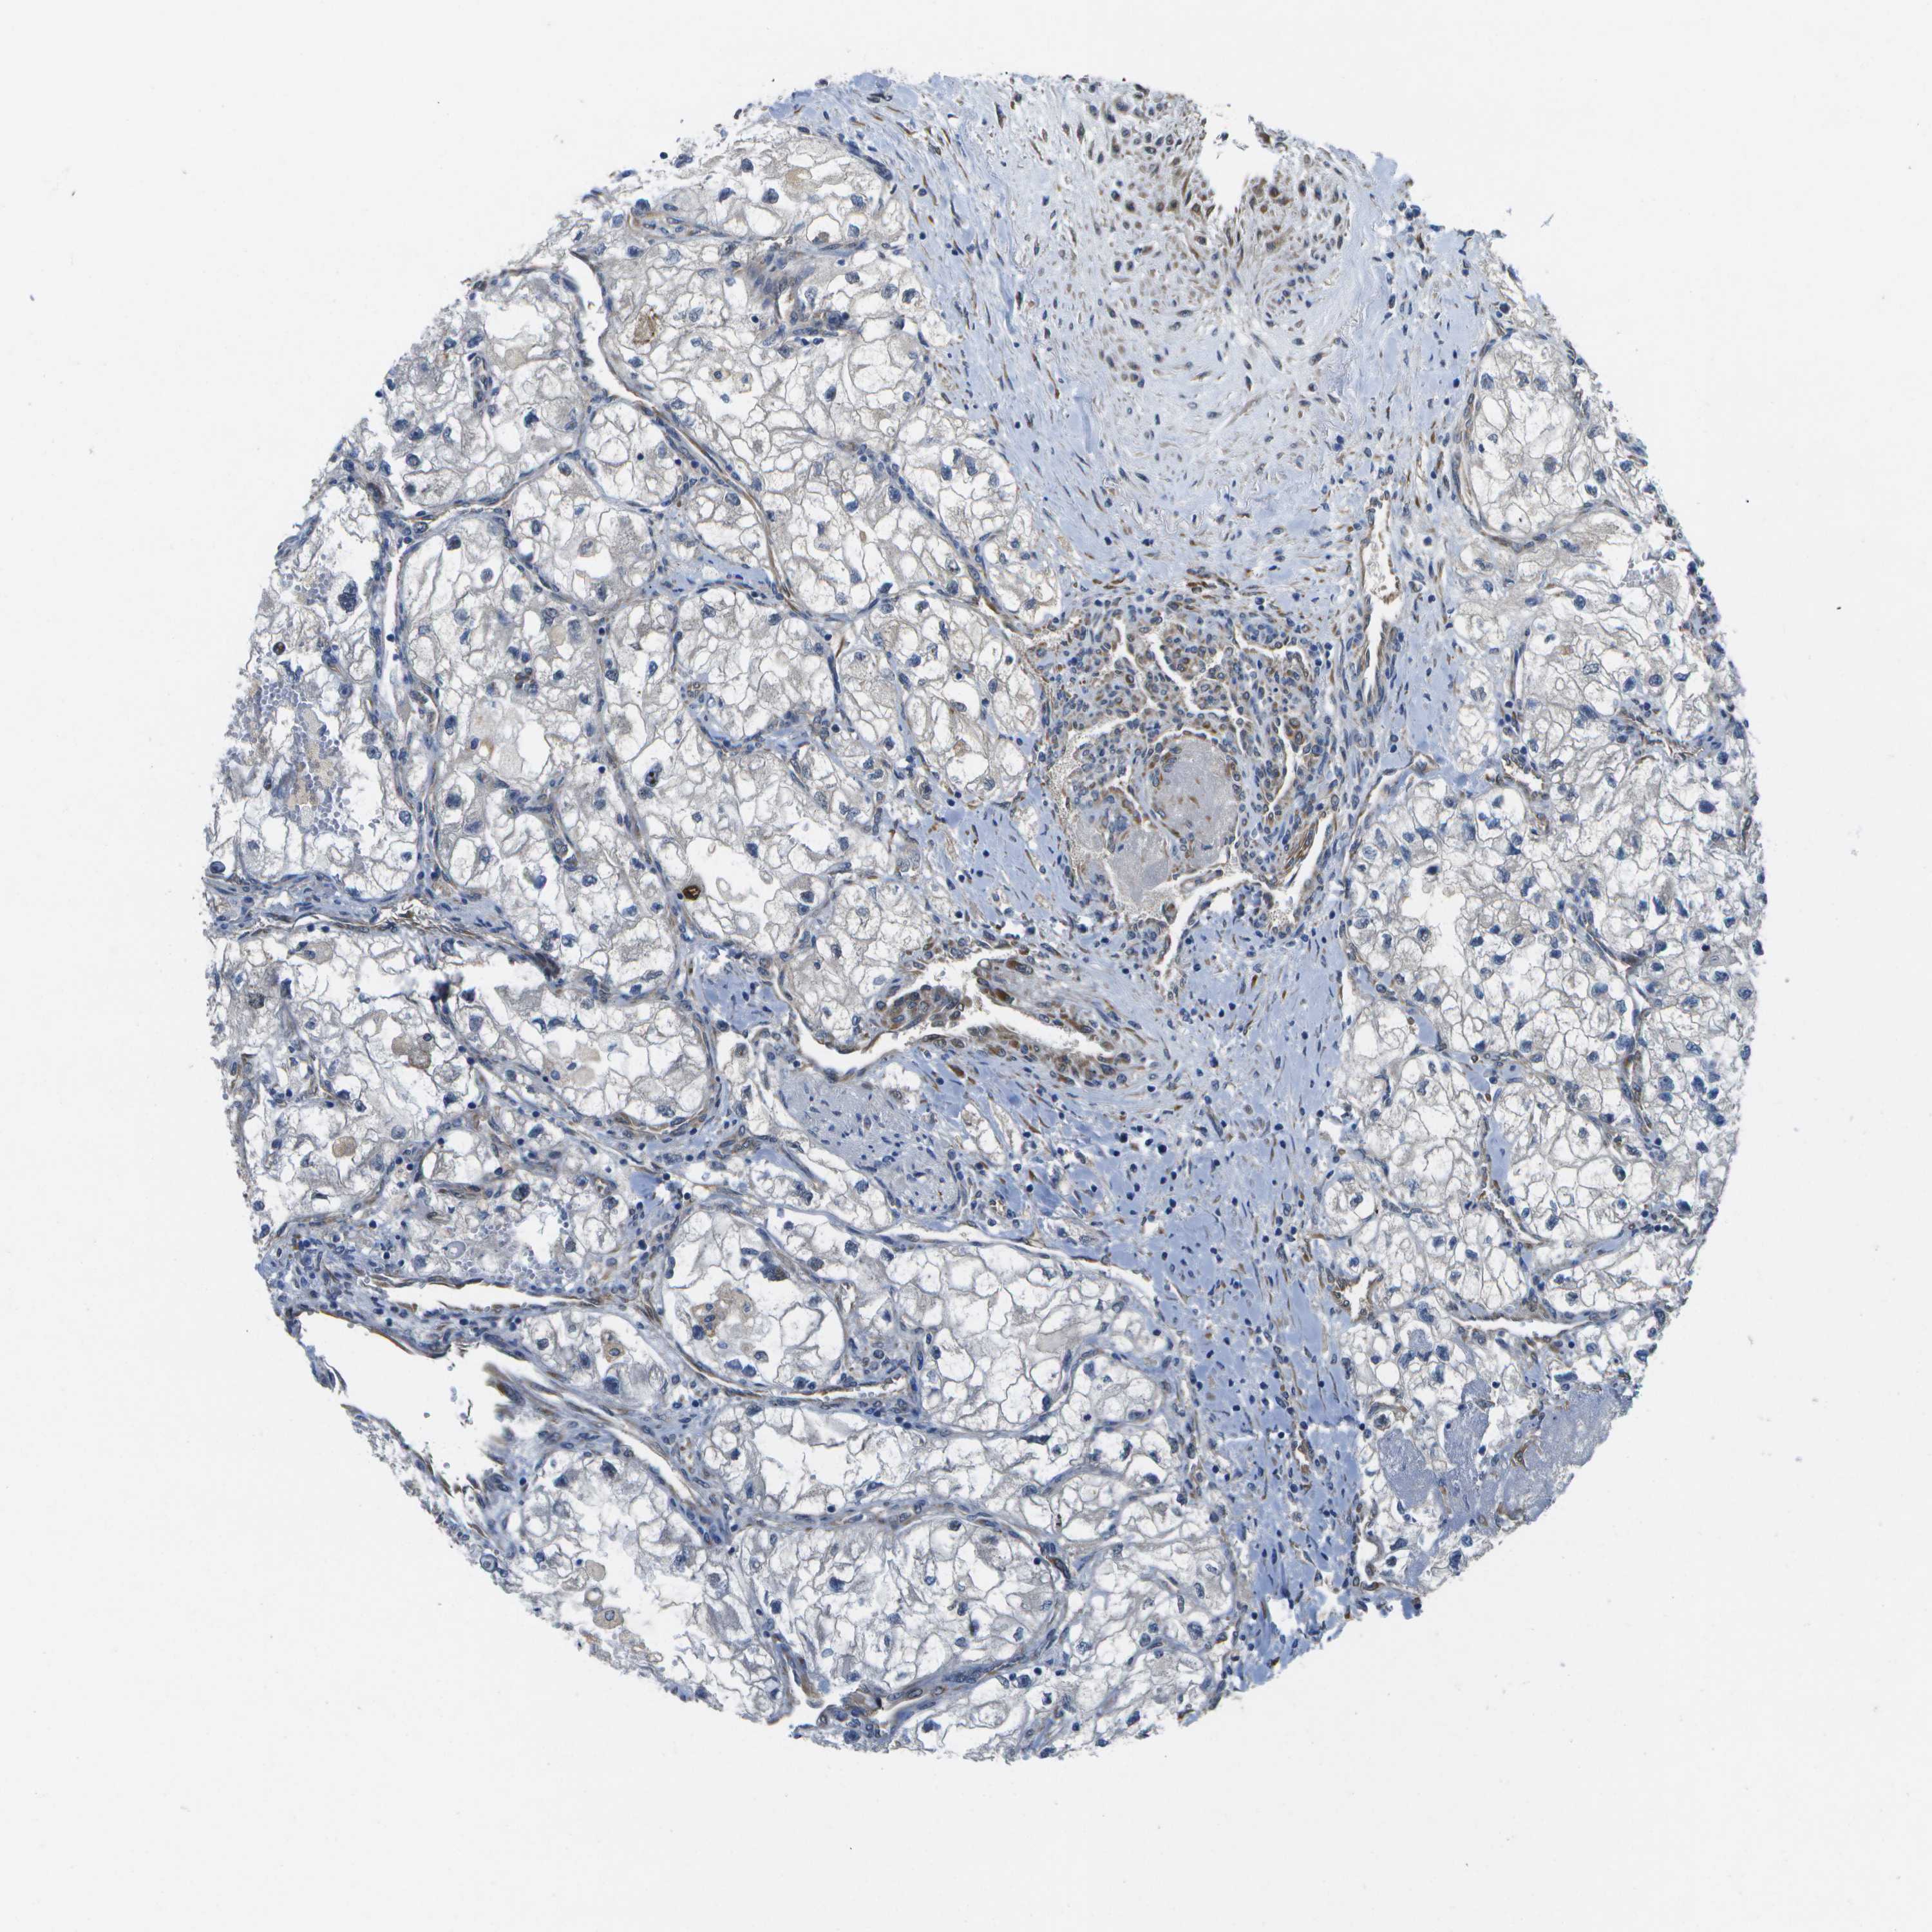

KIDNEY RENAL CLEAR CELL CARCINOMA (TCGA) - Interactive survival scatter ploti

The Survival Scatter plot shows the clinical status (i.e. dead or alive) for all individuals in the patient cohort, based on the same data that underlies the corresponding Kaplan-Meier plots. Patients that are alive at last time for follow-up are shown in blue and patients who have died during the study are shown in red.

The x-axis shows the expression levels (FPKM) of the investigated gene in the tumor tissue at the time of diagnosis. The y-axis shows the follow-up time after diagnosis (years). Both axes are complimented with kernel density curves demonstrating the data density over the axes. The top density plot shows the expression levels (FPKM) distribution among dead (red) and alive patients (blue). The right density plot shows the data density of the survived years of dead patients with high and low expression levels respectively, stratified using the cutoff indicated by the vertical dashed line through the Survival Scatter plot. This cutoff is automatically defined based on the FPKM cutoff that minimizes the p-score. The cutoff can be changed by dragging the vertical line or by entering a cutoff value in the square labeled "Current cut-off".

Under the Survival Scatter plot the p-score landscape (black curve; left axis) is shown together with dead median separation (red curve; right axis). Dead median separation is the difference in median mRNA expression between patients who have died with high and low expression, respectively. It is calculated as follows: median FPKM expression of dead patients with high expression - median FPKM expression of dead patients with low expression. This is intended to aid the user in visually exploring custom cutoffs and the associated p-scores and dead median separation.

Individual patient data is displayed and can be filtered by clicking on one or more of the category buttons on the top of the page. Categories describing expression level and patient information include: high, low, alive, dead, female, male and tumor stages. The scale of the x-axis can be toggled between linear and log-scale by clicking on the "x log" button. Mouse-over function shows TCGA ID, patient information and mRNA expression (FPKM) for each patient.

& Survival analysisi

Kaplan-Meier plots summarize results from analysis of correlation between mRNA expression level and patient survival. Patients were divided based on level of expression into one of the two groups "low" (under cut off) or "high" (over cut off). X-axis shows time for survival (years) and y-axis shows the probability of survival, where 1.0 corresponds to 100 percent.

P3H1 is potential prognostic, high expression is unfavorable in Kidney Renal Clear Cell Carcinoma (TCGA)

Best expression cut offi

: 20.15

P scorei

N/A

TCGA RNA samplesi

Average pTPM 16.8

Number of samples 521